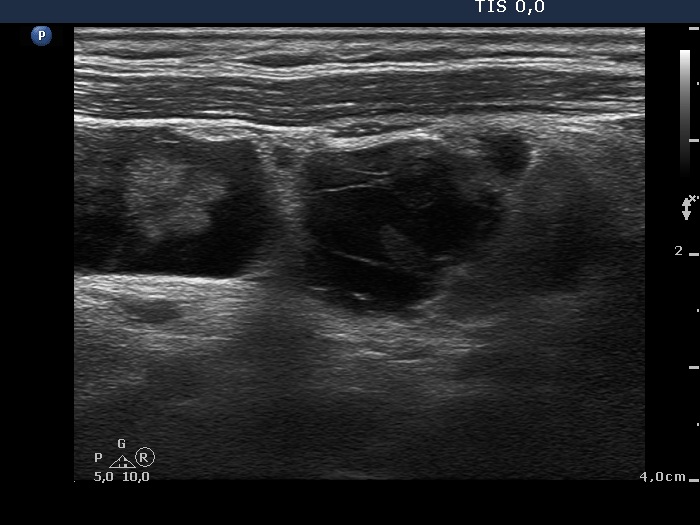

Intranodular hyperechogenic figures - case 779 (ultrasonographic picture 16)

Left side of the neck, longitudinal scan. There is a conglomerate of cystically degenerated metastatic lymph nodes.